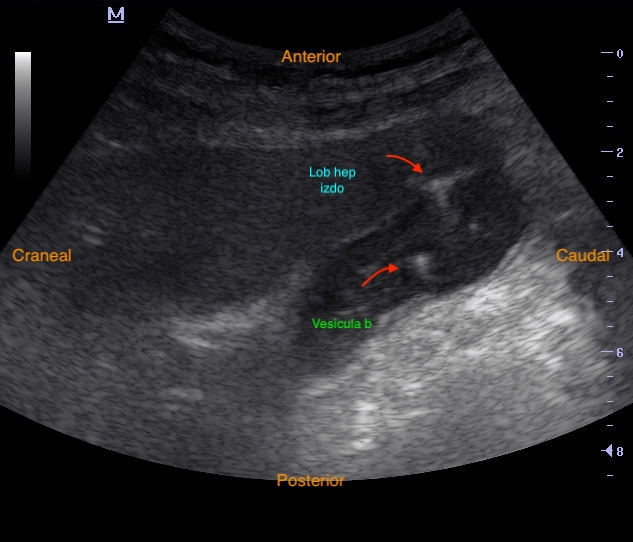

Se visualiza vesícula biliar con contenido hiperecogénico en su interior sugestivo de cálculos biliares, pared anterior engrosada (0,35 mm), con líquido perivesicular y fenómeno de ring-down en su interior (posible neumobilia). Colédoco distal dilatado, con signo del doble cañón, sin clara dilatación de conductos biliares intrahepáticos.